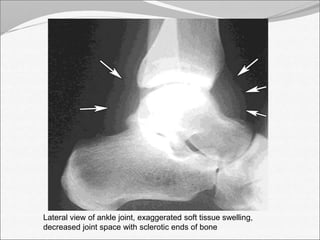

Lateral view of ankle joint, exaggerated soft tissue swelling,

decreased joint space with sclerotic ends of bone

• 13.

Lateral view ofankle joint, exaggerated soft tissue swelling, decreased joint space with sclerotic ends of bone